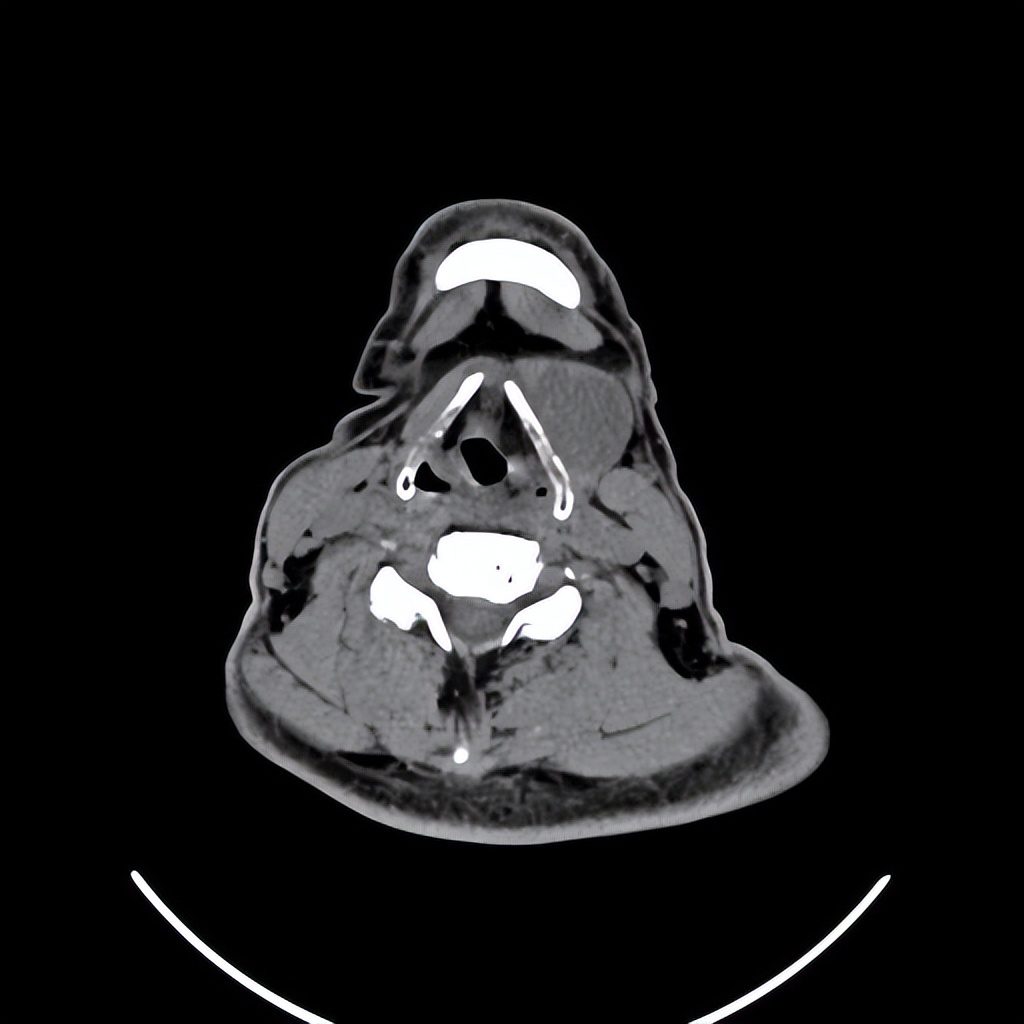

来自广东梅州的管叔,最近发现颈部肿物2周,不痒,不痛,自觉问题不大。但是肿物越来越大了,在家人的劝说下来到佛山复星禅诚医院耳鼻喉做了检查发现是颈部的先天性囊肿。

颈部肿物目前做小切口内镜微创手术比较适合,这样既能切除干净肿物,也会兼顾美观。关于颈部肿物如果您有任何的问题,欢迎留言和耳鼻喉郑立岗医生进一步交流。